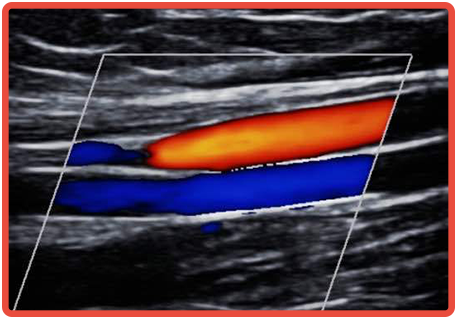

19 - Ecodoppler de Carótidas e Vertebral com Mapeamento de Fluxo a Cores

Detectar a presença de aterosclerose (placas de gordura, tecido fibroso) nas artérias que levam sangue ao cérebro.

COMO É FEITO![]()

Como o paciente deitado, examina-se a região do pescoço para analisar as artérias à procura de estreitamentos, placas de aterosclerose e obstruções, avaliando o fluxo sanguíneo. O exame é indolor e sem riscos para o paciente. Não é necessário preparo para realização do exame. Não é utilizada a radiação ou contraste.

INDICAÇÕES![]()

- Detectar precocemente a presença de aterosclerose, e assim, ajudar a decidir sobre o tratamento.

- Indicar e orientar a realização de cirurgia dessas artérias, em caso de obstruções importantes.

- Prevenção primária e secundária do AVC (acidente vascular cerebral) detectando-se placas que causam obstruções e podem ocasionar as isquemias cerebrais.

- Estudar as artérias oftálmicas quando há suspeita de cegueiras de etiologia isquêmica.